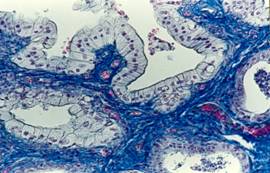

Microscopic, trasatura caracteristica este hiperplazia endometriala (hiperplazie glandulo-chistica) si transformarea epiteliului mucoasei uterine sub influenta hormonilor. Celulele sunt tumefiate, columnare, cu citoplasma spumoasa si pot prezenta nuclei picnotici. Uneori, epiteliul unistratificat se pliaza, capatand aspect pseudostratificat sau capata aspect de proliferare papilifera. In unele glande chistizate se instaleaza atrofia de compresiune a celulelor secretorii. Cand se produce interventia bacteriana, aglomerari de neutrofile pot fi surprinse in lumenul glandular sau infiltreaza difuz mucoasa uterina, traverseaza epiteliul mucoasei si se acumuleaza in lumenul organului.

In leziunile de intensitate medie apar cateva neutrofile in stroma endometriala si numeroase plasmocite si limfocite. In miometru se constata frecvent reactie perivasculara si leucocitoza a vaselor limfatice. Cand evolutia este mai grava, apar fenomene exsudative evidente concomitent cu raspunsuri reparatorii de tipul tesutului de granulatie, bogat in capilare de neoformatie. La cazurile cu liza endometrului se ajunge la infiltrarea miometrului cu neutrofile.

Piometru; glanda chistizata, infiltrat leucocitar abundent si reactie vasculara (hiperemie)

Hiperplazie glandulo-chistica; celule endometriale cu citoplasma spumoasa

Piometru; hiperplazie papilifera a epiteliului endometrial, hemoragie endometriala

Piometru; liza endometrului, hemoragie si infiltrat neutrofilic